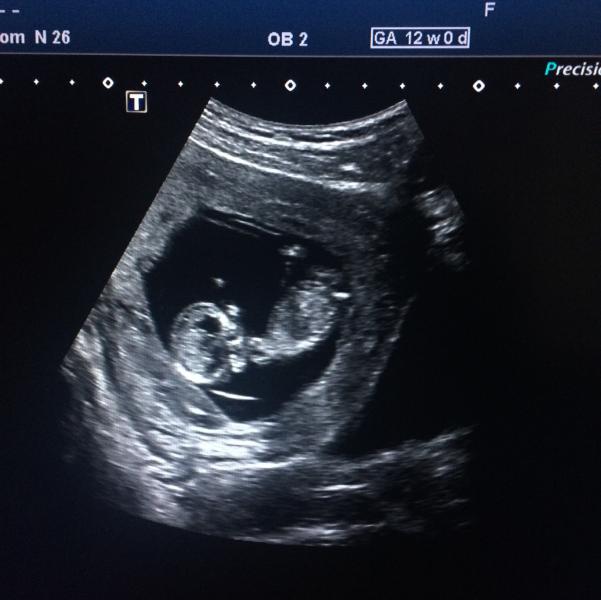

Это так странно, вроде такой небольшой срок. Но буквально позавчера начались интересные тыканья изнутри, как будто тыктыктык, маленькой ножкой. Сначала думала что это газики, но только газики обычно совсем с другой стороны у меня бывают 😄

И не мелкие пузырики.... А тык...... И тишина. Думала что колит что то, ну бывает такое, что колит внизу или тянет. Но это не колит и не тянет.

Я предполагаю, что это маленькие пинки, они слабые, они не чувствуются еще снаружи, но изнутри отчетливо чувствую. Н...